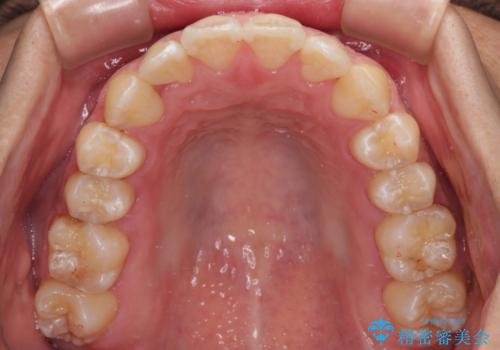

- 前歯のデコボコを気にして来院された患者様です。

歯列としてはワイヤー装置でもインビザラインでも対応可能でしたが、インビザラインが苦手とする上顎側切歯(真ん中から2番目の歯)の舌側転位が顕著でした。

治療の確実性を上げるために、インビザライン開始前に上顎のワイヤー装置にて舌側転位を解消し、その後インビザラインにて矯正治療を行うこととしました。

前歯のデコボコが早めに改善され、スムーズに治療を終えることができました。